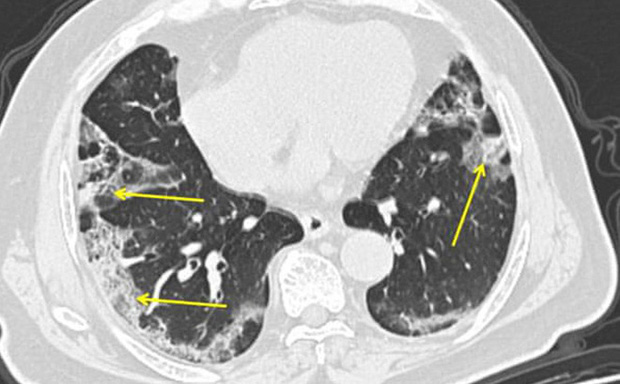

Bức ảnh cho thấy bản chụp CT của một bệnh nhân nhiễm COVID-19. Viêm phổi gây ra bởi virus corona khiến phổi có những vết mờ dễ thấy ở viền ngoài phổi. Ảnh: Mount Sinai Hospital/AP

Ông Wilson cho biết có bằng chứng cho thấy viêm phổi gây ra bởi COVID-19 có thể trở nên rất nghiêm trọng. Theo ông Wilson, các ca viêm phổi loại này thường bị ảnh hưởng tới toàn bộ phổi, thay vì một số phần nhỏ.